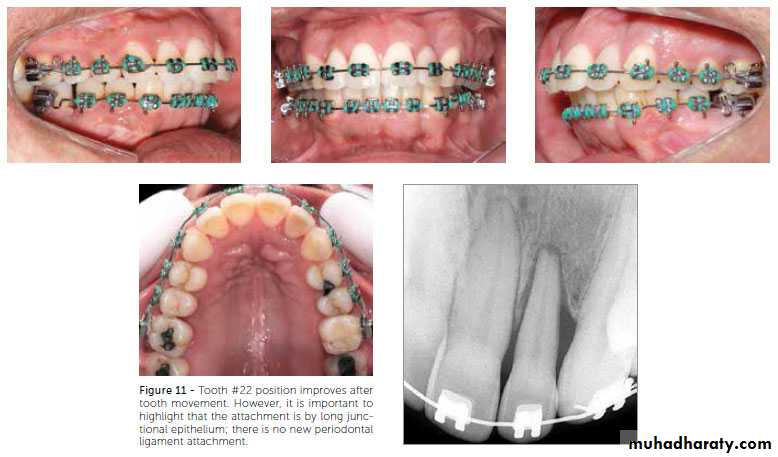

While the use of retainers incorporating posterior bite blocks has been recommended for prolonged retention of anterior open bite malocclusions with unfavorable growth patterns, there is currently a lack of scientific evidence to support this.Patients with a history of periodontal disease or root resorption

In patients with previously treated severe periodontal disease, permanent retention is advised. For those with minimum to moderate disease, a more routine retention protocol can be used. There is evidence of an increased risk of deterioration of lower incisor alignment post-retention in cases with root resorption or crestal bone loss. These cases may therefore benefit from prolonged retention.Growth modification treatment

Fixed retainers are indicated for long-term retention of the labial segments, particularly when there is reduced periodontal support, and for retention of a midline diastema. Fixed retainers are discreet and reduce the demands on patient compliance. However they are associated with failure rates of up to 47%, particularly on upper incisors when there is a deep overbite. In addition, calculus and plaque deposition is greater than with removable retainers. Fixed retainers therefore require long term maintenance.Flexible spiral wire retainers allow differential tooth movement and are particularly useful for patients with loss of periodontal support. Current orthodontic opinion recommends either the use of 0.0215 inch multistrand wire, or 0.030 - 0.032 inch sandblasted round stainless steel wire.